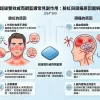

一、什麼是少精、弱精、無精?

在探討「少精、弱精、無精原因」之前,需先了解基本定義:

少精癥(Oligospermia):精子濃度低於1500萬/ml

弱精癥(Asthenozoospermia):精子活動力低於40%

無精癥(Azoospermia):精液中完全沒有精子

這三種情況是影響男性生育能力的主要因素。

少精、弱精、無精

二、少精、弱精、無精原因(核心解析)

1.睪丸功能異常(核心因素)

睪丸是精子生成的主要器官,一旦功能受損,會直接影響精子數量與品質。

5.生殖道阻塞(無精癥常見原因)

無精癥分為「阻塞性」與「非阻塞性」。

6.遺傳與染色體異常